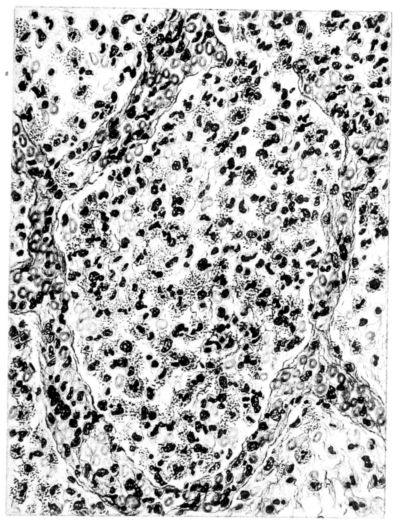

FIG. III. AUTOPSY NO. 90. DRAWING FROM A LESION OF THE TRACHEA (SOMEWHAT OLDER THAN THAT ILLUSTRATED IN FIGURE II). THE MUCOSA IS ENTIRELY LACKING. CONGESTION AND EDEMA ARE THE STRIKING FEATURES IN THE SUBMUCOSA. THE NECROTIZING PROCESS HAS EXTENDED INTO THE MUCUS GLANDS. THIS IS SHOWN IN THE LOWER PICTURE.

The changes are less marked, perhaps, in the trachea than in its finer ramifications. The mucosa is constantly more or less destroyed and large areas, usually focal, are entirely devoid of their epithelial covering. This is replaced by a sparse exudate, composed largely of red blood cells, mucus, a small amount of fibrin, and nuclear fragments (Fig. II). It may dip into the submucosa for a short distance, but usually these indentures are associated with the ducts of the mucous glands into which the inflammatory reaction extends. A more striking feature than the exudate, however, is the edema and the congestion of the submucosa. The loose areolar tissue of the submucosa is spread widely apart, and throughout it distended blood vessels are very conspicuous. Occasionally such a vessel is broken and actual hemorrhage appears in the submucosa. Occasionally, too, the inflammation extends down the duct to the mucous gland itself, and here, also, aplastic inflammatory reaction is evident, inasmuch as the acini now stain intensely red with the cells undifferentiated from each other and specked here and there by broken remains of the dead nuclei (Fig. III). After the disease has continued for a short period, even at the end of five or six days, some regeneration of the epithelial lining may be seen (3) (Fig. IV). But despite this, the acute picture persists, and there goes on, side by side, an attempted repair characterized by epithelial regeneration and the same evidence of acute change. Since the lesion is essentially a superficial one, scars or contractures of any extent are not encountered in the trachea, even in examples of the disease that have ended fatally only after many weeks.[4]